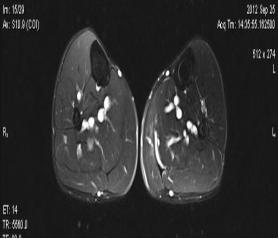

典型病例:患者,男,40岁,体能训练致左小腿肌肉撕裂伤并巨大血肿,给予脉冲磁疗、中频电疗和下肢肌肉训练指导后,血肿逐渐消退,两个月后肌肉恢复正常,继续参加训练。